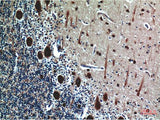

Applications IHC-p

IHC 1:100-200